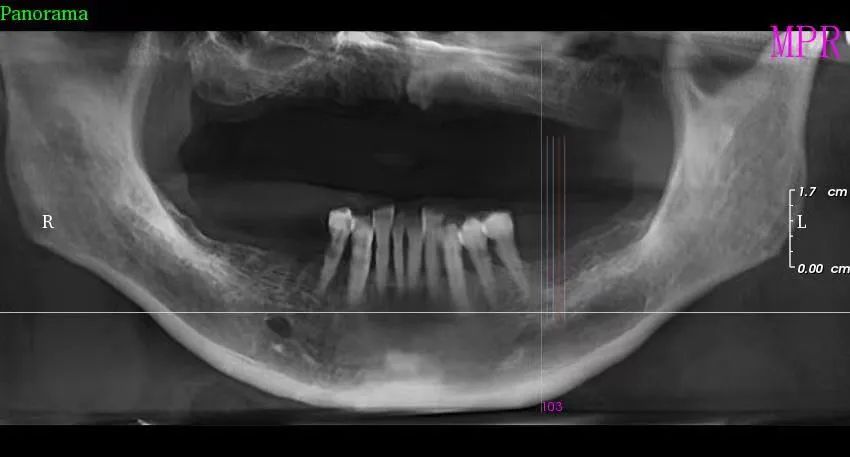

三、种植牙技术

目前,社会上很多人被牙齿缺失所困扰,牙齿缺失不但影响人的咀嚼和语言功能,对于人的面部美观也是一种影响,甚至有些人因缺失牙齿而不愿意张口说话,种植牙被誉为人类“第三副牙齿”,因其舒适、美观、功能好而被缺牙患者追捧。经卫建委批准,我院于2023年3月18日正式开展种植牙技术,开展当天门诊手术7例共计14颗植体,术后1天回访患者表示无红肿、无疼痛症状,术后7天回访一切良好无异常,术后10天拆线创口愈合良好,自开展口腔种植手术以来,有许多患者纷纷到科里进行相关咨询和检查,更是不断有患者预约意向种植,我院严格按照江西省医疗保障局、江西省卫生健康委员会关于公布实施口腔种植类医疗服务价格有关事项的通知—赣医保字《2023》3号文件执行操作,在手术诊疗中,严格操作流程,减少感染风险。我院口腔种植技术的成功和发展,不仅完善了传统牙齿修复技术的不足,而且在功能与美观上给了人们崭新的体验,我院致力于提供一站式口腔种植诊疗服务,必将为本县及周边缺失牙患者找回美丽、自信的微笑。

种植前 种植后